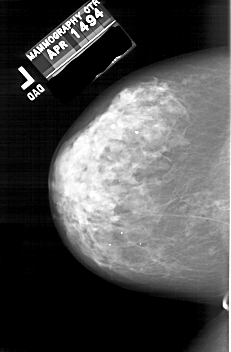

A_2000_1.LEFT_MLO

LEFT_MLO LINES 6121 PIXELS_PER_LINE 4216 BITS_PER_PIXEL 12 RESOLUTION 43.5 NON_OVERLAY